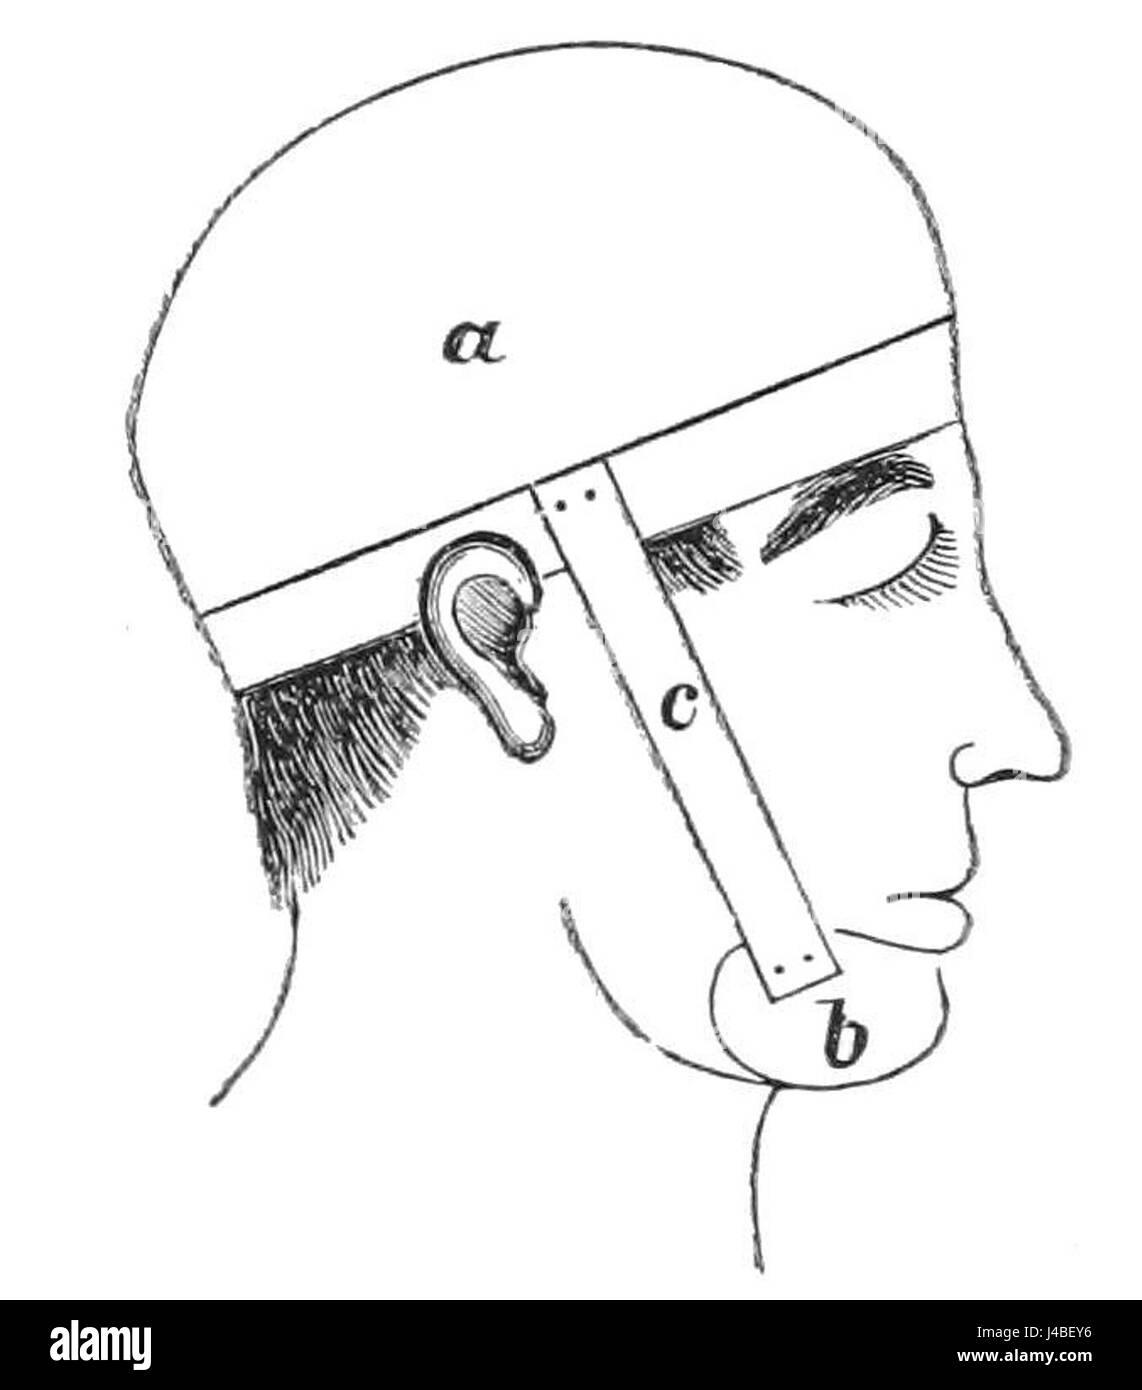

PSM V11 D725 Head brace to eliminate snoring Stock Photohttps://www.alamy.com/image-license-details/?v=1https://www.alamy.com/stock-photo-psm-v11-d725-head-brace-to-eliminate-snoring-140394778.html

PSM V11 D725 Head brace to eliminate snoring Stock Photohttps://www.alamy.com/image-license-details/?v=1https://www.alamy.com/stock-photo-psm-v11-d725-head-brace-to-eliminate-snoring-140394778.htmlRMJ4BEY6–PSM V11 D725 Head brace to eliminate snoring